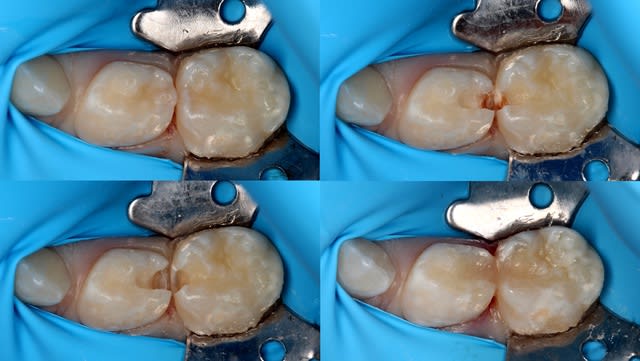

Peu de temps après, il fait une exposition pulpaire sur une 26 présentant une carie pourtant à peine dentinaire. L'exposition baigne dans la salive, la digue n'est pas posée, contrairement aux consignes du service. "Gentil", j'explique que l'exposition était évitable et constitue un mauvais facteur pour le pronostic de la dent, d'autant plus au vu de la contamination salivaire. Faciès bovin, aucune réaction. J'explique en d'autres termes : "Tu vois cette petite fille de 7 ans ? Tu comprends que sa 26 est probablement perdue au long terme par ton acte ?". Aucune réaction. J'insiste et lui demande sincèrement : "Ça ne te fait rien ? Tu ne te sens pas un peu triste ?". Il répond nonchalamment : "J'sais pas, faut qu'j'aille chercher une digue, c'est ça ?".

Img 8798  2  kdehll - Eugenol

Pulpo11 rfxfdi - Eugenol

Img 8920  2  lqxvfg - Eugenol

De deux, tu penses que ton iconographie m'impressionne? Il n'y a rien de très compliqué.

De trois , la digue elle sert à quoi? C'est pour le fond bleu c'est ça ?

Je suis vraiment content que tu me dises ça. Cette iconographie me demande énormément de temps sur des enfants de 4-6 ans et dans le flux d'un cabinet libéral. Comme ce n'est "pas compliqué" et que tu as plein de conseils pour les enseignants, tu va pouvoir m'aider à préparer les cours ?

Je t'invite à rechercher "split dam technique". Particulièrement adapté pour les soins en dentition temporaire et mixte. https://www.google.fr/?gws_rd=ssl#q=split+dam+technique